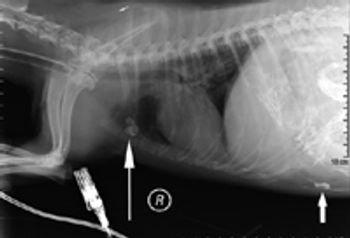

When performing a complete cardiac evaluation, a minimum of two views are necessary: lateral and either VD or DV.